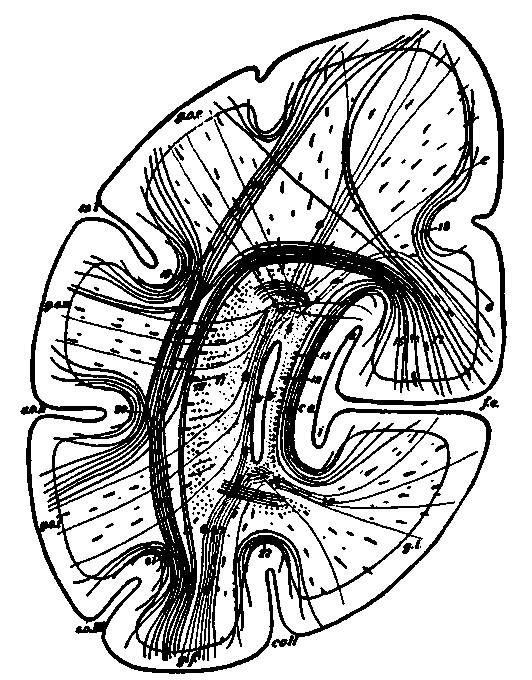

| 10. | Schematic frontal section through the occipital lobe illustrating manifold connections in a single lobe | 116 |

| 11. | Isolated cell from human spinal cord | 117 |